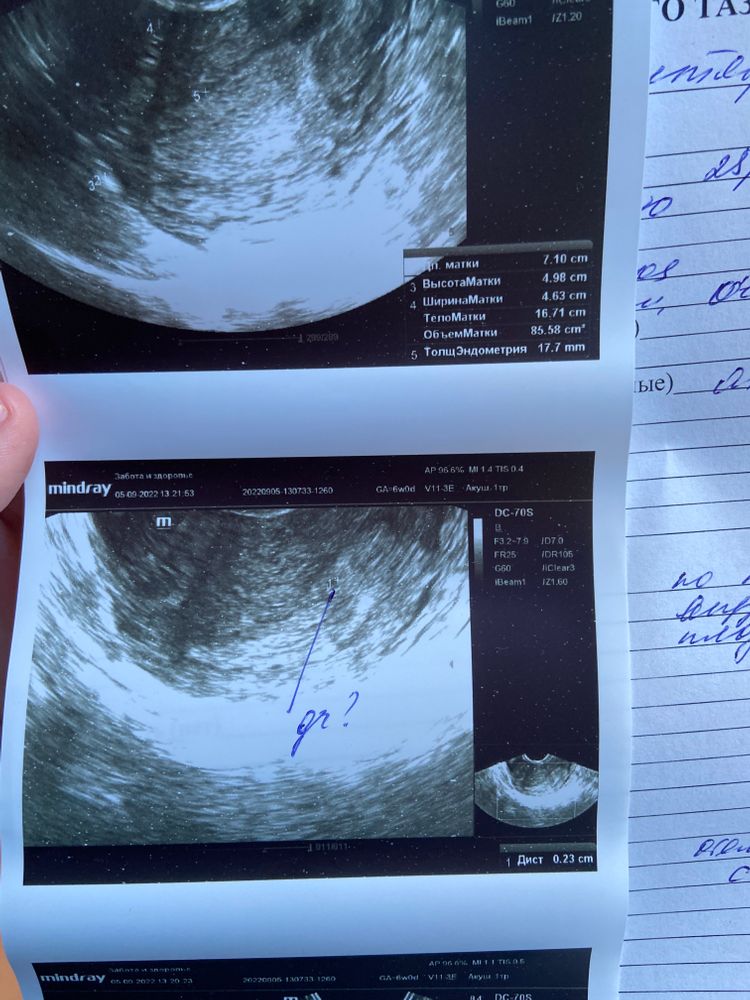

Сходила сегодня на УЗИ, до этого была в четверг(01.09), но там было ничего не видно и мне сказали прийти в понедельник(05.09). 3го числа сдала хгч, результат был 158, о беременности узнала 29.08 по слабой полоске на тесте.

Сегодня сдала ХГЧ и пришла на УЗИ. Вот что непонятно: врач увидела в матке только плодный мешок без плодного яйца.. Это вообще как, реально? Врач напугала внематочной беременностью, мол плодный мешочек может быть в матке, а ПЯ вообще в трубе.. Я в замешательстве, очень переживаю, не знаю что делать. Может у кого-то так было? Снимки узи прикрепляю

У вас нашли плодное яйцо без желточного мешочка. Какой размер пя точно не видно на фото.

Аня, нет, у девушки совершенно другая ситуация. У нее видели жёлтое тело в яичнике. У вас судя по протоколу и снимку УЗИ - в матке плодное яйцо. Пока пустое - что с вашим хгч - норма

А что там может быть видно если Диаметр плодного Яйца всего 2.1 мм.????!!! Что то ваш врач заговорился, кадеться он сам не понял что написал. Сдайте хгч в динамике, а если переживаете то через неделю к другому врачу на узи сходите. Но на узи нечего делать при хгч меньше 1000. А эмбрион видет при хгч больше 10000 обычно